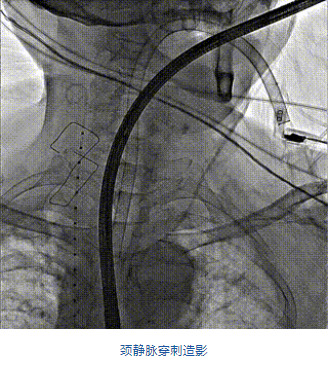

團(tuán)隊(duì)前期經(jīng)過(guò)多次討論,制定了周密的手術(shù)策略和預(yù)案。由于患者已是近九旬的超高齡老人,傳統(tǒng)外科開(kāi)胸手術(shù)風(fēng)險(xiǎn)極高,純介入經(jīng)血管三尖瓣替換能夠明顯減少創(chuàng)傷。術(shù)中陳茂及馮沅教授結(jié)合體表定位在造影指示下精準(zhǔn)穿刺右側(cè)頸靜脈并預(yù)置兩把血管縫合器。成功建立經(jīng)皮血管入路后在食道超聲和DSA的引導(dǎo)下順利完成人工瓣膜植入,術(shù)后超聲和造影顯示人工三尖瓣同軸性良好,瓣架固定牢靠,無(wú)反流和瓣周漏,平均跨瓣壓差降為1mmHg。術(shù)畢收緊預(yù)置的血管縫合器縫線完成止血,縫合效果滿(mǎn)意,在手術(shù)室即刻拔除氣管插管。